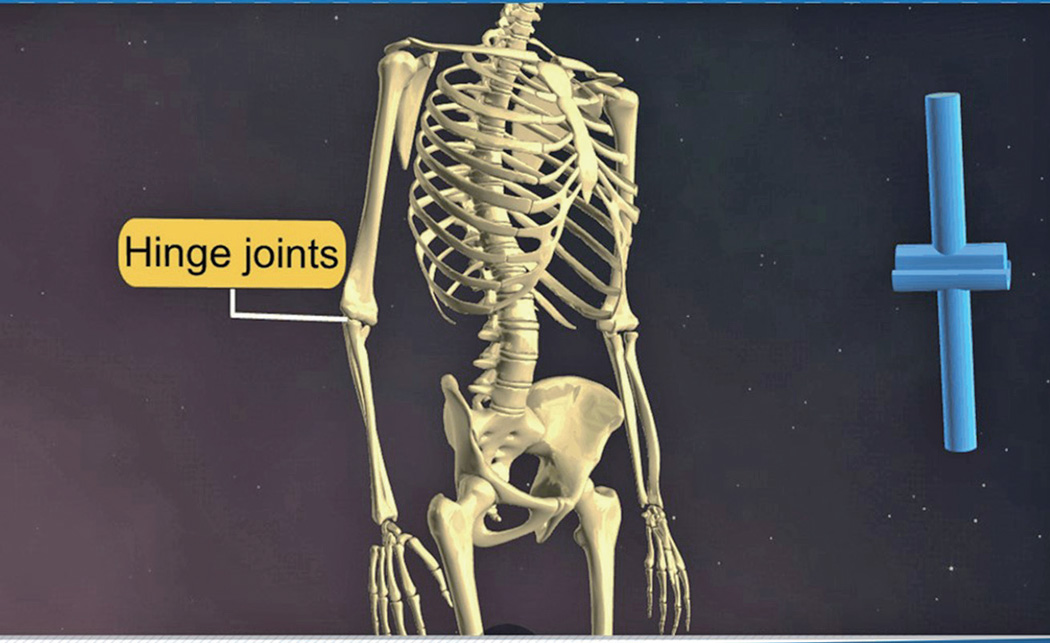

이와 같이 잘 움직이지 않는 부동관절에 비해 가동관절은 실제 움직이는 관절이기 때문에 참관절(true joint)이라고 부릅니다. 이 가동관절은 움직임의 종류에 따라서 여러 가지로 나눕니다.

- 가동관절② 경첩관절